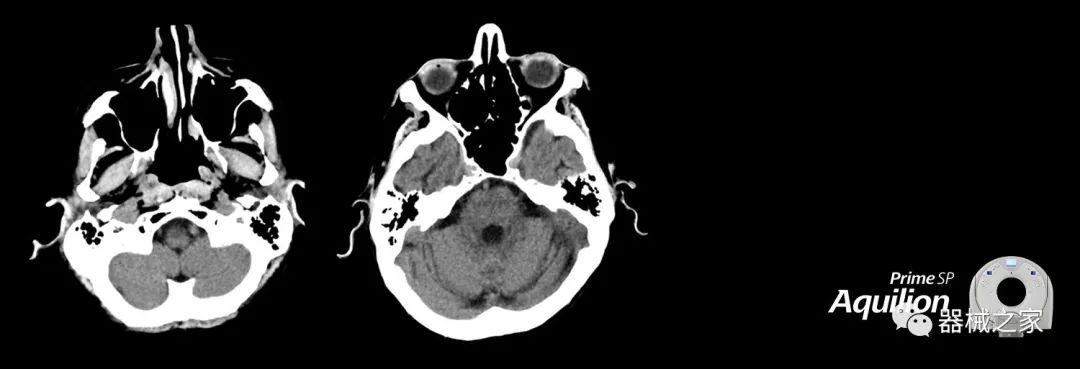

在以患者為中心的放射腫瘤學領(lǐng)域,計算機斷層掃描(CT)的可訪問性,可重復(fù)性和靈活性至關(guān)重要。為了建立這些價值,佳能醫(yī)療系統(tǒng)美國公司現(xiàn)在正在擴大其放射腫瘤學CT模擬產(chǎn)品,包括Aquilion Prime SP和Aquilion Lightning 80高級CT系統(tǒng)。除了Aquilion LB之外,Aquilion Prime SP和Aquilion Lightning 80現(xiàn)在還包括放射治療(RT)選項,可為腫瘤學規(guī)劃提供高質(zhì)量的CT成像和精密工具。

Aquilion Prime SP使設(shè)施能夠處理具有挑戰(zhàn)性的案例,同時為員工提供快速,靈活和高效的解決方案。

兩個CT系統(tǒng)均采用0.5 mm x 80排PUREViSION探測器技術(shù)(可配置并從80-160現(xiàn)場升級),78 cm孔徑,50 cm視野,AIDR(自適應(yīng)迭代劑量減少)3-D和SEMAR(單個)能量金屬神器減少)技術(shù)。